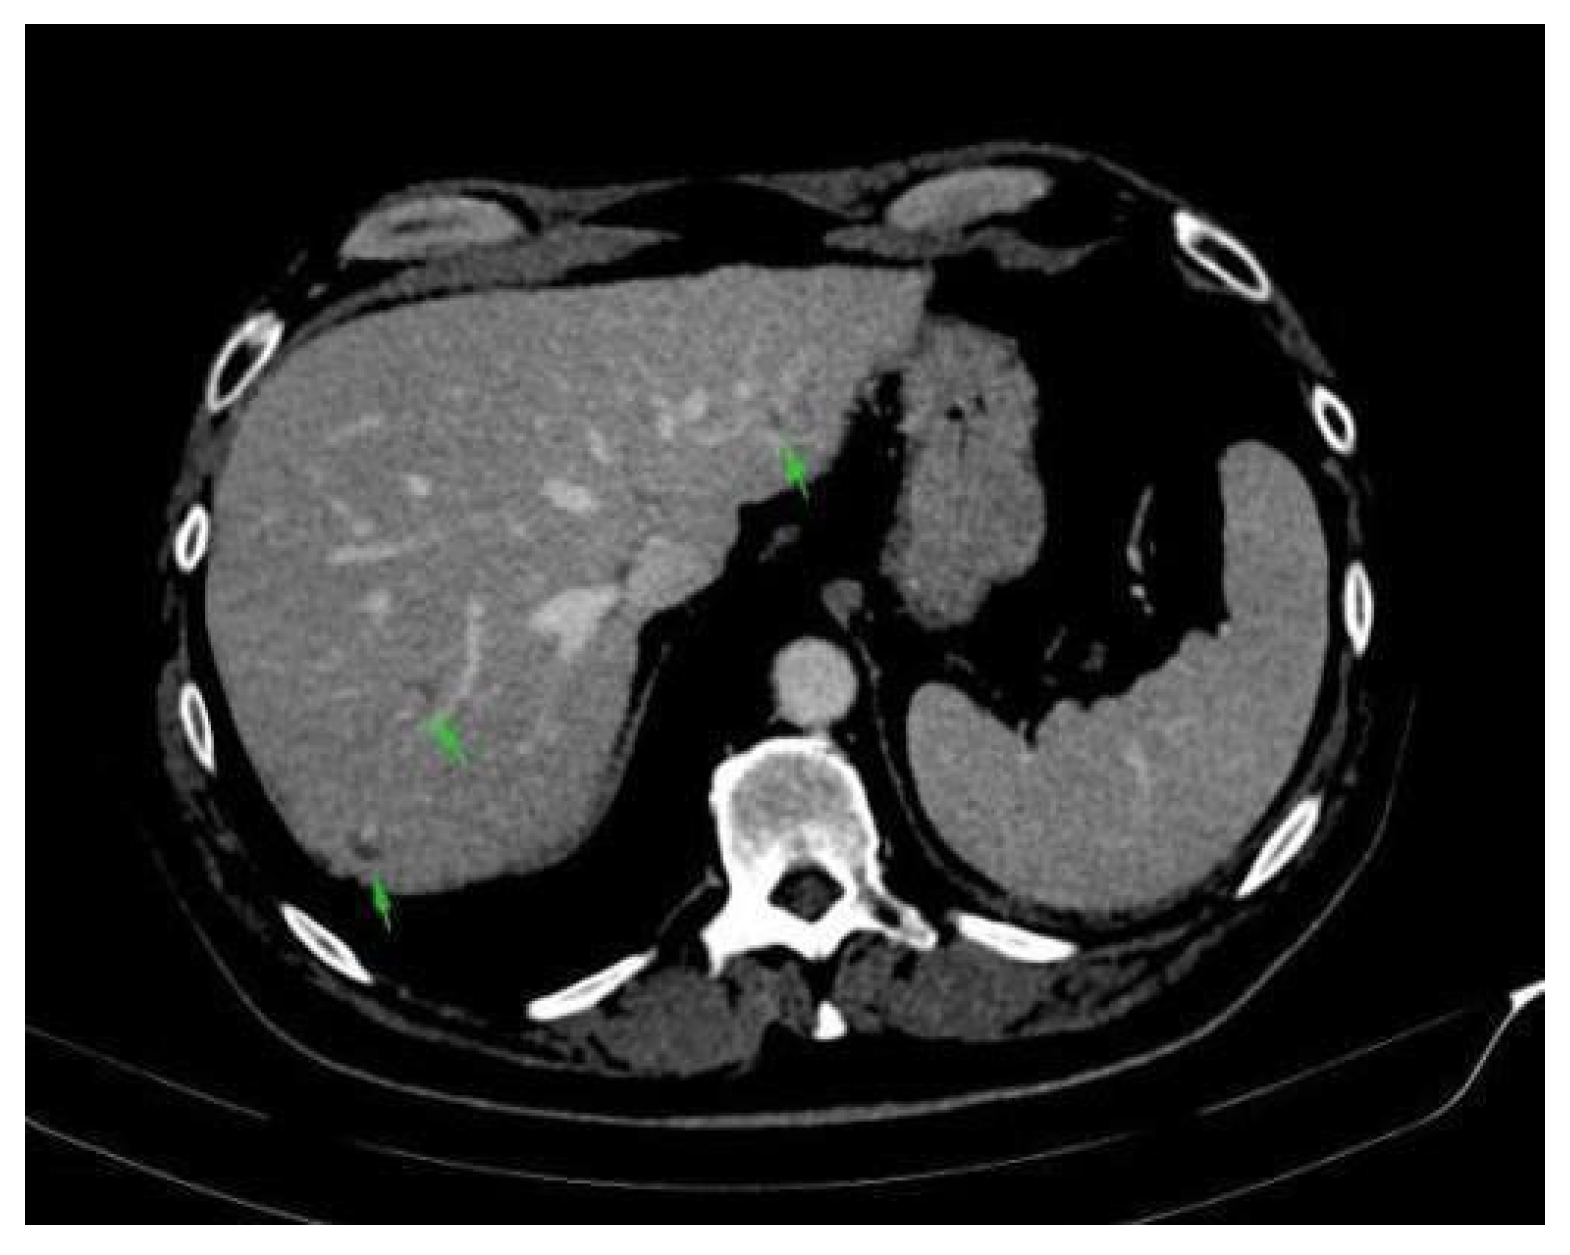

2. Case Presentation